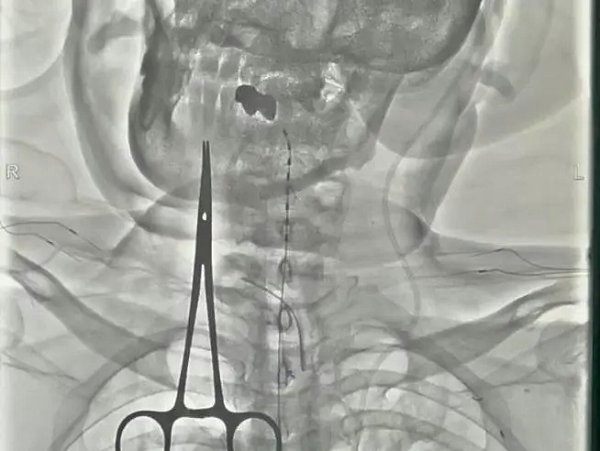

4月27日在医院复合手术室,由寿记新主任医师、管海博主治医师共同完成颈段及腰段短时程脊髓电极植入术,为患者尽早拔除气管套管、完全清醒、站起来、能走路、回归生活奠定了良好基础。

病例二:老年男性,1个月前“因高处坠落致颅脑及胸段脊髓损伤后双下肢截瘫”,由外院转入神经外科一病区,后经积极评估、讨论后给予胸段椎管扩大减压+内固定术。术后虽左下肢可稍活动,但右侧下肢仍无明显活动、大小便排便困难,需持续卧床,家属进行照顾。患者及家属治疗愿望迫切,1周前科室再次充分讨论下一步治疗方案,最后决定行腰段短时程脊髓电刺激手术治疗。